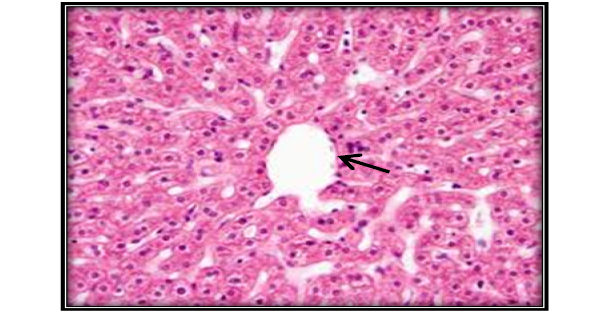

Liver section for untreated mouse (control) showing central vein ( ) surrounded with hepatic cord (H&E 200X).